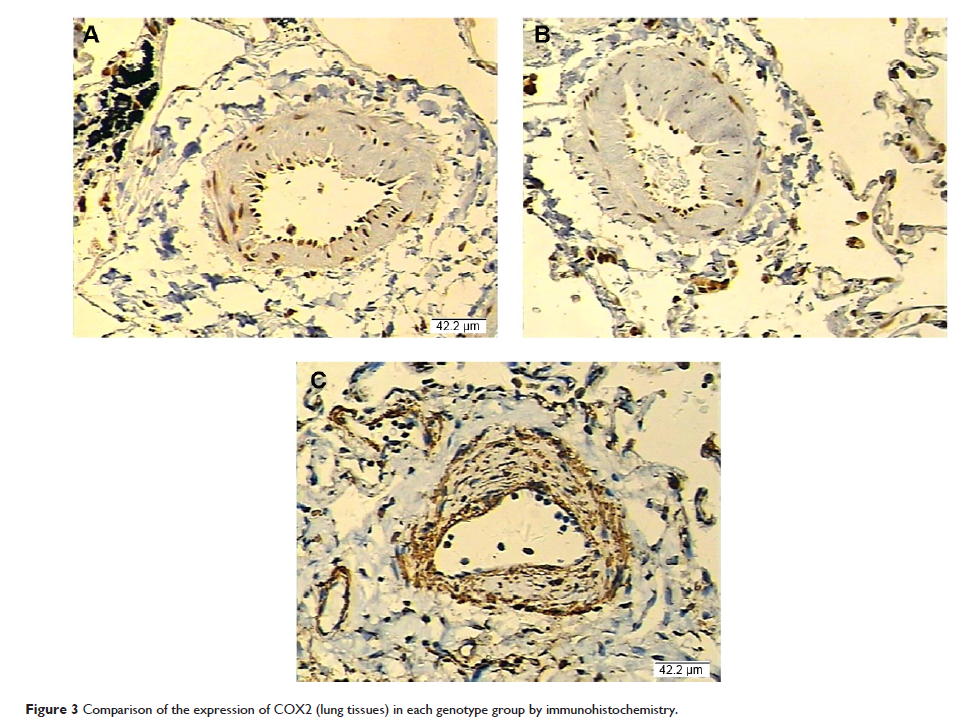

- 作者:Ran Wang, Min Li, Sijing Zhou, Daxiong Zeng, Xuan Xu, Rui Xu, Gengyun Sun

- 期刊:International Journal of Chronic Obstructive Pulmonary Disease